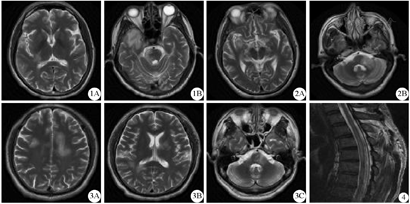

1A:右侧侧脑室后脚长T2异常信号,1B:右侧颞叶、右侧脑干长T2异常信号;2A:右侧丘脑、颞叶长T2异常信号,2B:左侧延髓、小脑长T2异常信号;3A:双侧大脑半球长T2异常信号,3B:右侧侧脑室后脚、左侧基底节区长T2异常信号,3C:脑干及左侧桥臂片状长T2异常信号,边缘不清

患者1男性,42岁,因"反复头晕、行走不稳8月余,再发20 d"于2017年3月16日入院。患者8个月前因出现头晕、言语不清于2016年6月2日在我科第1次住院,头颅MRI平扫+增强扫描(2016年6月2日)示右侧颞叶、丘脑及脑干异常信号(图1),考虑脱髓鞘病变,予甲强龙500 mg冲击3 d后剂量阶梯递减,出院后口服泼尼松50 mg渐递减至停用,症状基本消失。20 d前患者劳累后再次出现头晕,行走不稳,言语不清,伴恶心、呕吐,拟"脱髓鞘脑病"收入院。既往史:5年前有视神经炎病史,双眼视力下降,现遗有视物模糊;有甲状腺功能减退病史,现每日口服优甲乐100 μg治疗;否认高血压、糖尿病、冠心病等病史,否认烟酒等不良嗜好。体检:构音障碍,双眼水平、垂直眼震,左侧外展稍受限;四肢肌力5级,左上肢腱反射(+++),余肢体腱反射(++),左侧巴氏征(+);双侧共济运动差(左侧明显),Romberg征:睁眼、闭眼均为阳性。头颅MRI检查(2017年3月17日)示右侧颞岛叶、丘脑及脑干多发异常信号(图2)。腰穿测颅内压为130 mmH2O(1 mmH2O=0.0098 kPa),脑脊液蛋白0.61 g/L(正常值:<0.40 g/L),脑脊液白细胞11个/μL。血清+脑脊液寡克隆区带分析未见异常,脑脊液鞘内合成指数0.68(正常值:<0.7),血清抗MOG抗体IgG阳性(滴度1∶10)(杭州欧蒙医学检验所间接免疫荧光法检测;正常值:阴性)(下述检测方法及参考值均相同),脑脊液抗MOG抗体IgG阳性(滴度1∶1)。血及脑脊液抗水通道蛋白4(AQP4)抗体均阴性。考虑为MOG-AD,再次予甲强龙500 mg冲击后剂量阶梯递减治疗,症状很快基本消失,出院前复查血清抗MOG抗体IgG为阴性。

患者2男性,41岁,因"头晕伴视物不清1周"于2017年3月13日入院。患者1周前开始出现头晕,视物成双,双侧下肢无力,双手麻木,渐加重。既往有"病态窦房结综合征"病史,有颈椎病史。体检:神清,眼球活动正常,向右视可见水平眼震,双侧下肢肌力4级,双侧病理征(-),共济运动检查正常。入院后头颅MRI检查(2017年3月14日)示双侧大脑半球、脑干及左侧桥臂片状长T2异常信号,边缘不清(图3);DWI序列上稍高异常信号;注射造影剂钆喷酸葡胺(Gd-DTPA) 15 mL后增强扫描示部分病灶呈轻度斑点、片絮状强化。腰穿测颅内压110 mmH2O,脑脊液蛋白0.69 g/L(正常值:<0.40 g/L),脑脊液白蛋白353.0 mg/L(正常值:<350.0 mg/L)、IgG 41.9 mg/L(正常值:<34.0 mg/L),脑脊液细胞学检查未见明显异常。脑脊液抗MOG抗体IgG阳性(滴度1∶3.2),血清抗MOG抗体IgG阳性(滴度1∶10);血及脑脊液抗AQP4抗体均阴性。考虑为MOG-AD,予甲强龙500 mg冲击后剂量阶梯递减治疗,症状逐渐好转后出院。

患者3男性,61岁,因"急起双下肢无力6 d"于2017年4月6日入院。患者自2017年3月底持续1周咽痛、流脓鼻涕,发热至38 ℃左右。2017年4月1日患者突然出现双下肢无力,但尚能挪动,大便便秘、小便潴留,症状渐加重,表现为双下肢完全瘫痪,以"脊髓病变"收入院。既往于1992年有类似症状,诊断为"脊髓炎",治疗措施不详,后未遗留明显后遗症。体检:神清,双下肢肌力0°,肚脐以下深感觉消失,平乳头连线水平以下痛觉消失;双下肢腱反射(++),双侧巴氏征(+)。入院后胸髓MRI检查(2017年4月7日)示胸髓4~8内条片状长T2异常信号(图4)。血清抗MOG抗体IgG阳性(滴度1∶10);血及脑脊液抗AQP4抗体均阴性;血清抗自身免疫性脑炎相关抗体及副肿瘤综合征相关抗体均阴性。考虑为急性脊髓炎,予甲强龙500 mg冲击后剂量阶梯递减治疗,并辅以改善微循环、营养神经等治疗。2017年5月12日出院时双下肢肌力4级,能拖步独立行走,出院前复查抗中枢神经系统脱髓鞘病变相关抗体均为阴性。